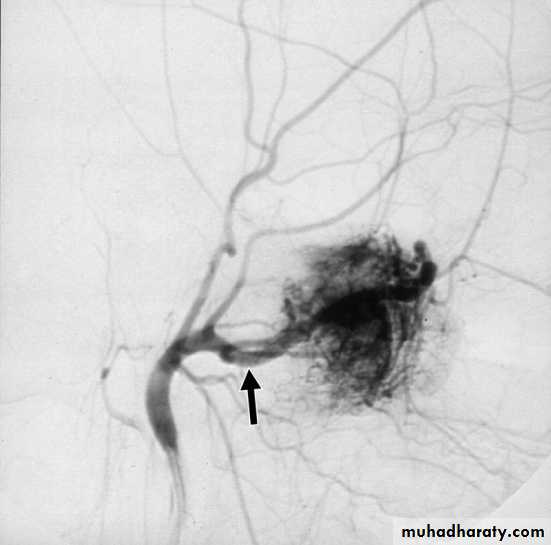

c. External carotid arteriography.

1. Surgical excision Haemorrhage is the main danger of operation, so adequate blood should be prepared before the operation.2. Embolization is indicated preoperatively to control the vascularity of the tumour.